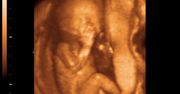

Zdjęcia płodu - twarze